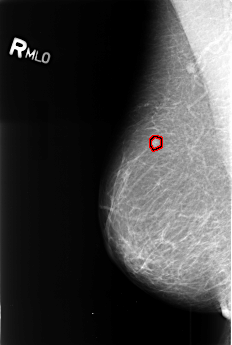

B_3394_1.RIGHT_MLO

RIGHT_MLO LINES 4480 PIXELS_PER_LINE 3008 BITS_PER_PIXEL 12 RESOLUTION 50 OVERLAY

FILE: B_3394_1.RIGHT_MLO.OVERLAY

TOTAL_ABNORMALITIES 1

ABNORMALITY 1

LESION_TYPE MASS SHAPE IRREGULAR MARGINS ILL_DEFINED

ASSESSMENT 4

SUBTLETY 4

PATHOLOGY MALIGNANT

TOTAL_OUTLINES 1

BOUNDARY